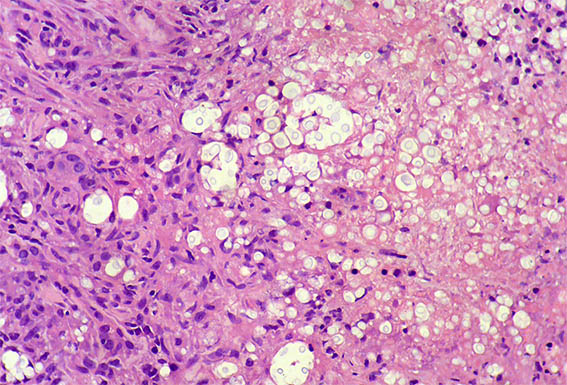

The patient is a 42-year-old man with acute kidney injury of unclear aetiology, creatinine 3.5 mg/dL, BUN: 54 mg/dL; edema in lower limbs, one week of evolution. He does not report other symptoms. As relevant history, the patient was diagnosed with HIV infection 20 days earlier and started antiretroviral therapy 2 weeks ago, which raises the possibility of acute tubulointerstitial nephritis secondary to drugs.

Look at the images of the renal biopsy:

Figure 3. H&E, X200.